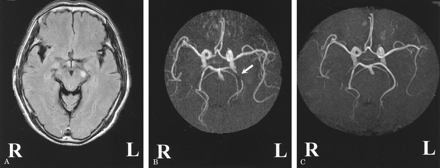

一个65岁的老人与高血压发达轻微程度的构音障碍和右手的疲弱。神经系统检查显示中央麻痹性痴呆的右脸,舌头,上肢无共济失调。Fluid-attenuated反转恢复成像(1.5特斯拉,日立医疗层云II)显示标记hyperintensity信号在左大脑脚(图,一个)。先生血管造影术(MRA),使用一个三维飞行时间序列,披露违规左侧基底动脉狭窄的环境(P2)段(见图B岁),与之前相比MRA(参见61年图中,C)。

图。(一)轴向fluid-attenuated反转恢复成像。(B)崩溃成像的大脑血管成像(MRA)显示狭窄左先生P2段(箭头所指)。(C)崩溃以前大脑血管摄影的成像。

腔隙性梗死大脑脚很少发生,可能导致dysarthria-one-hand弱点。1大脑脚的循环是由沟通后的穿支动脉和花梗的穿通动脉和大脑后动脉弯曲的树枝。那些射孔和圆周分支源自precommunical (P1)或P2的大脑后动脉。2我们的图片表明身体的同侧的P2的狭窄段可能导致脑花梗的梗死病人。